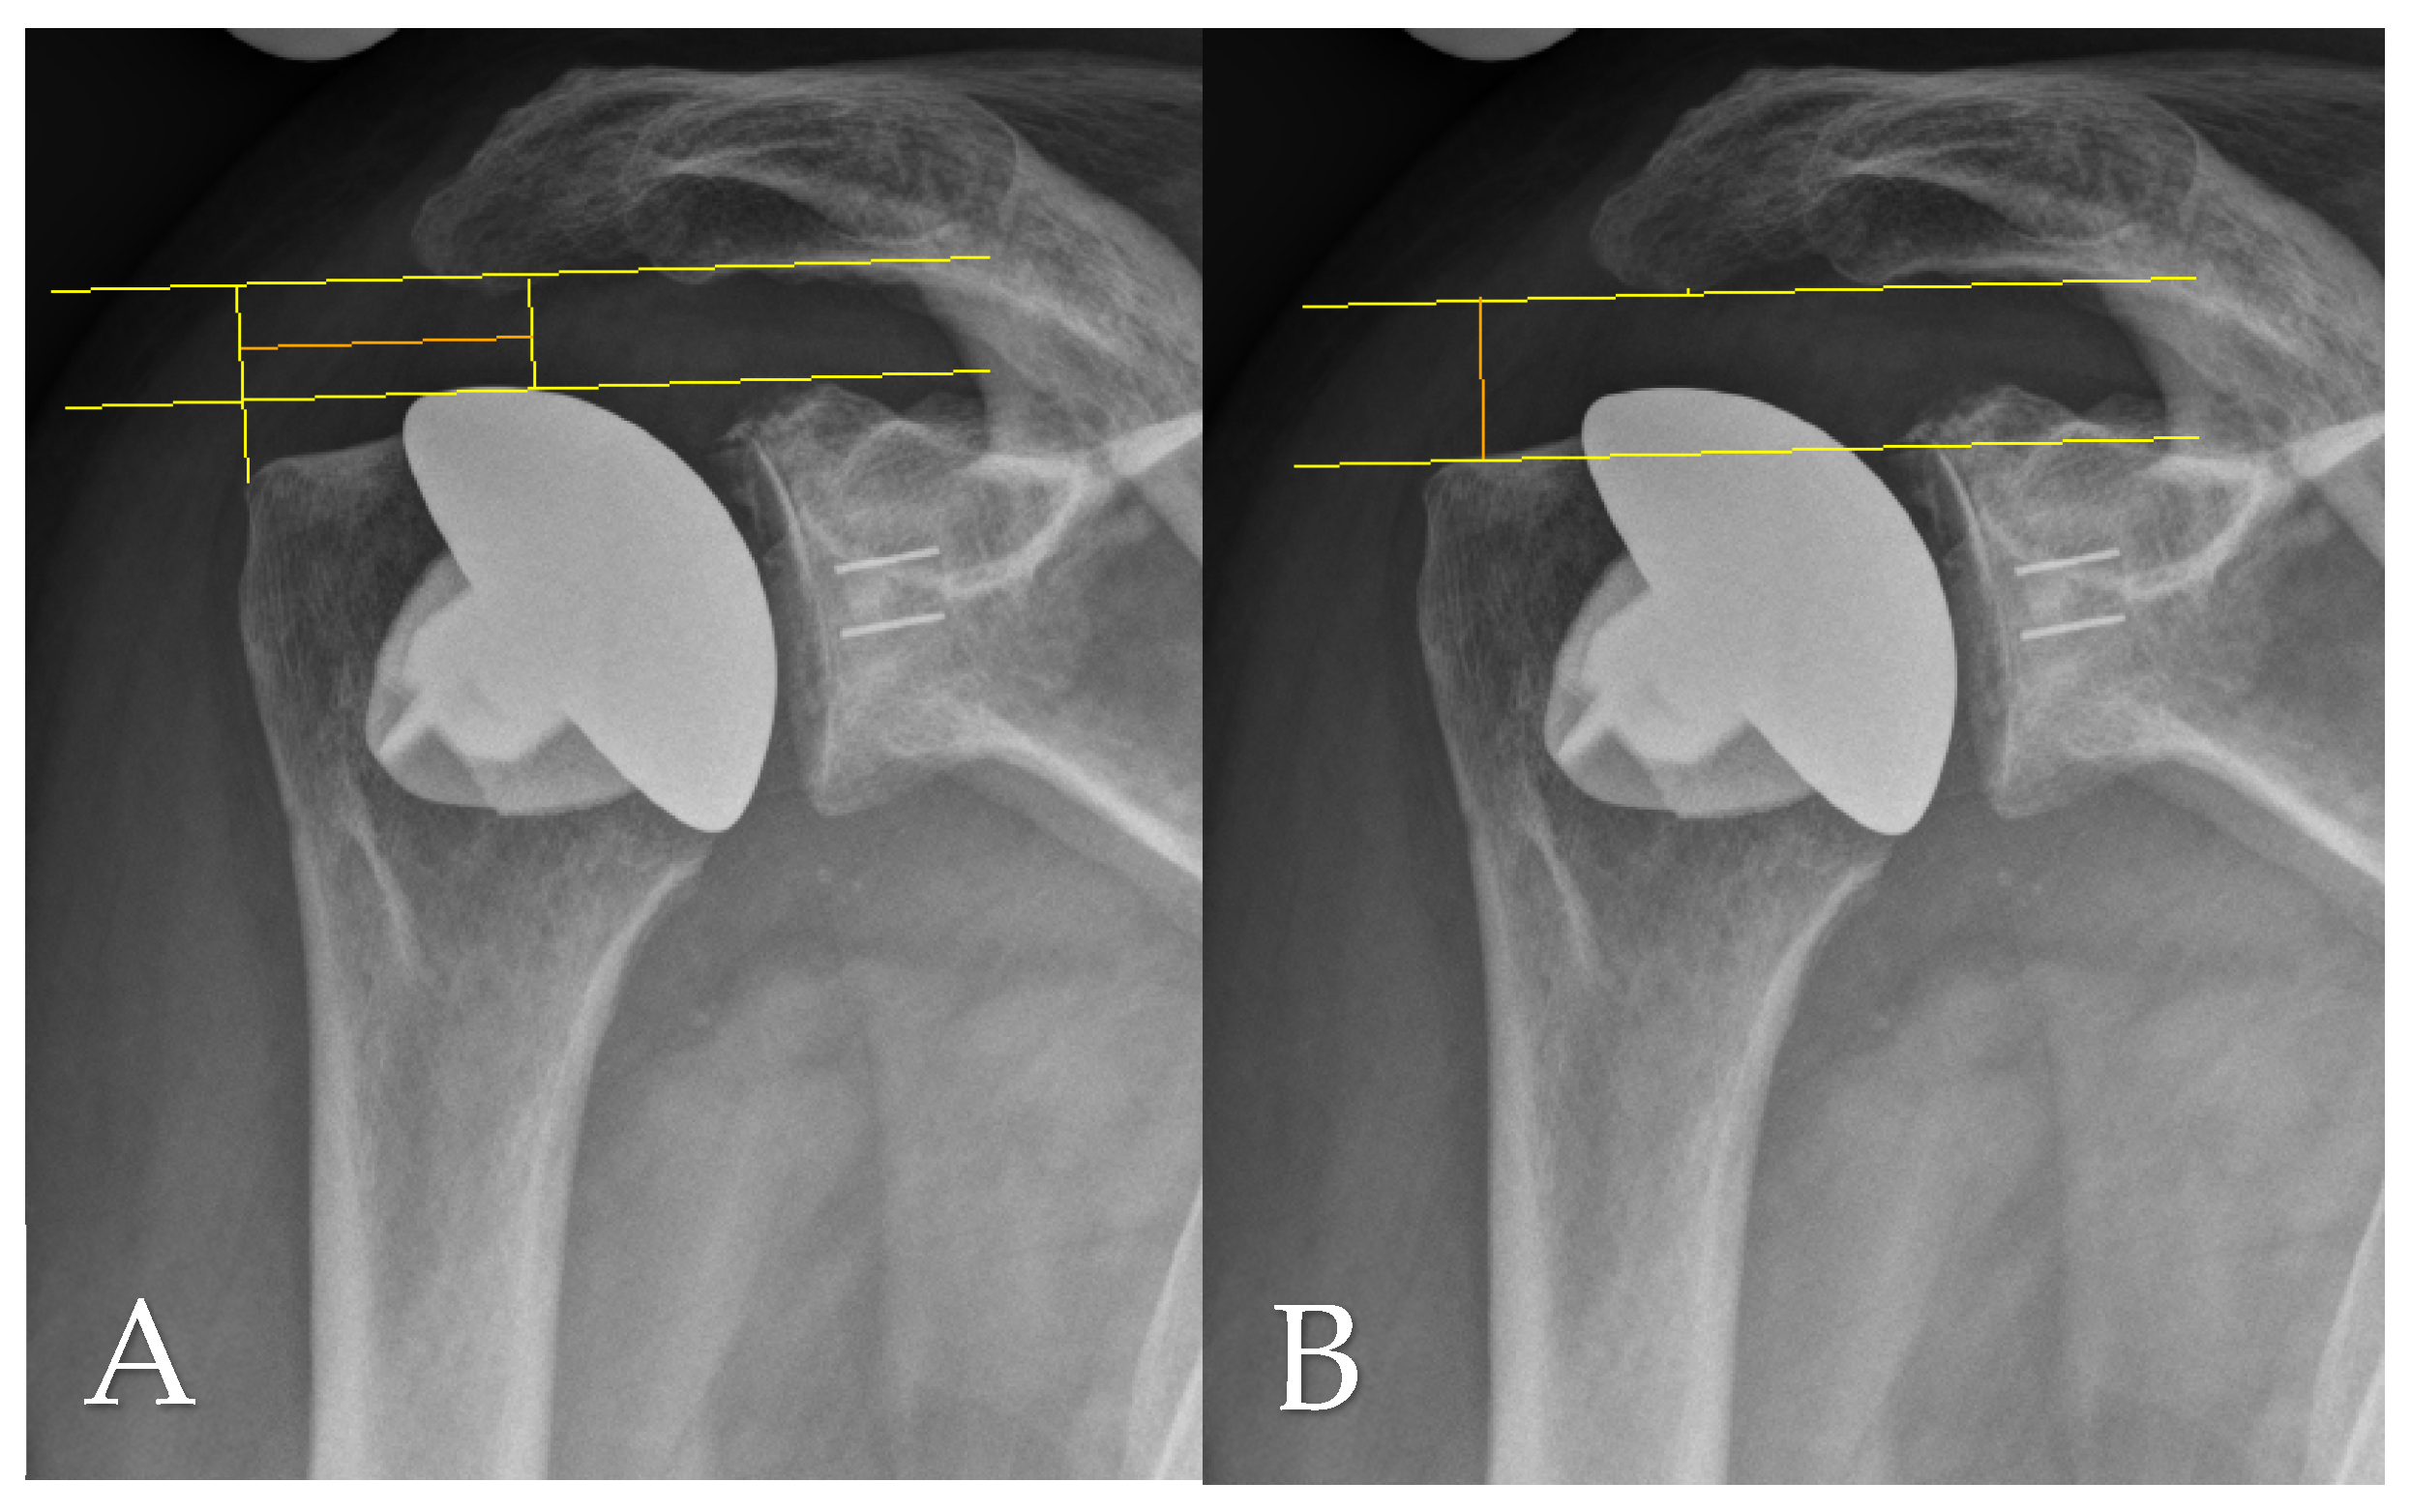

2.2. Radiographic and Clinical Evauation

2.4. Radiographic Assessment